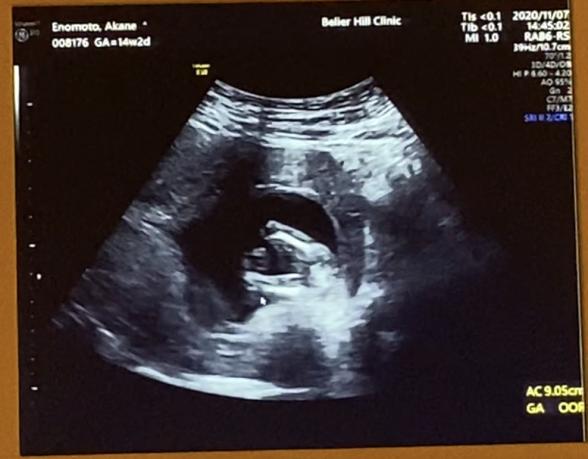

妊娠14週2日の時のエコーです☆ こちらのエコーで性別はわかりますか? 〜っぽい。でも構いません^ - ^ 旦那と両方の名前を考えていて どちらでもとっても大歓迎なのですが 男子が女子か気になって質問させていただきました! 宜しくお願いします^^

拝見させていただきましたが、申し訳ありません。はっきりとはわかりませんでした。

次回の健診の時に先生にも確認をしてみていただけたらと思います。エコーの時に同じようにお股の方を上手く見せてくれるようでしたら、はっきりとわかるのではないかなと思います。